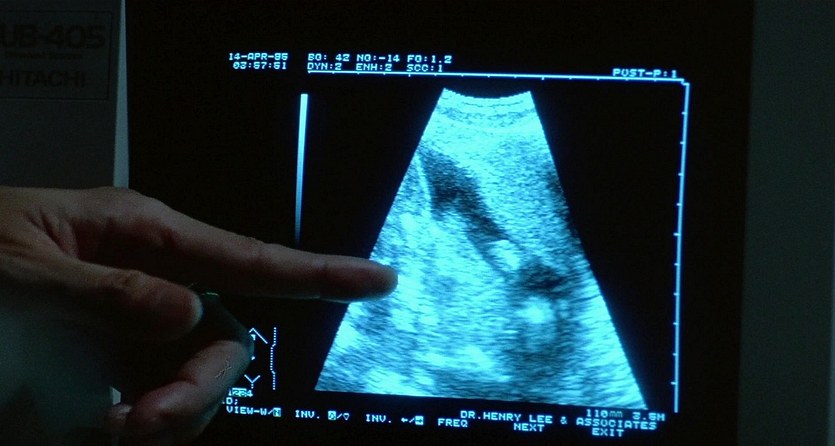

Great Adventurers (1995)

Name: The.Adventurers.1995_08862

Source: Blu-ray 1080p